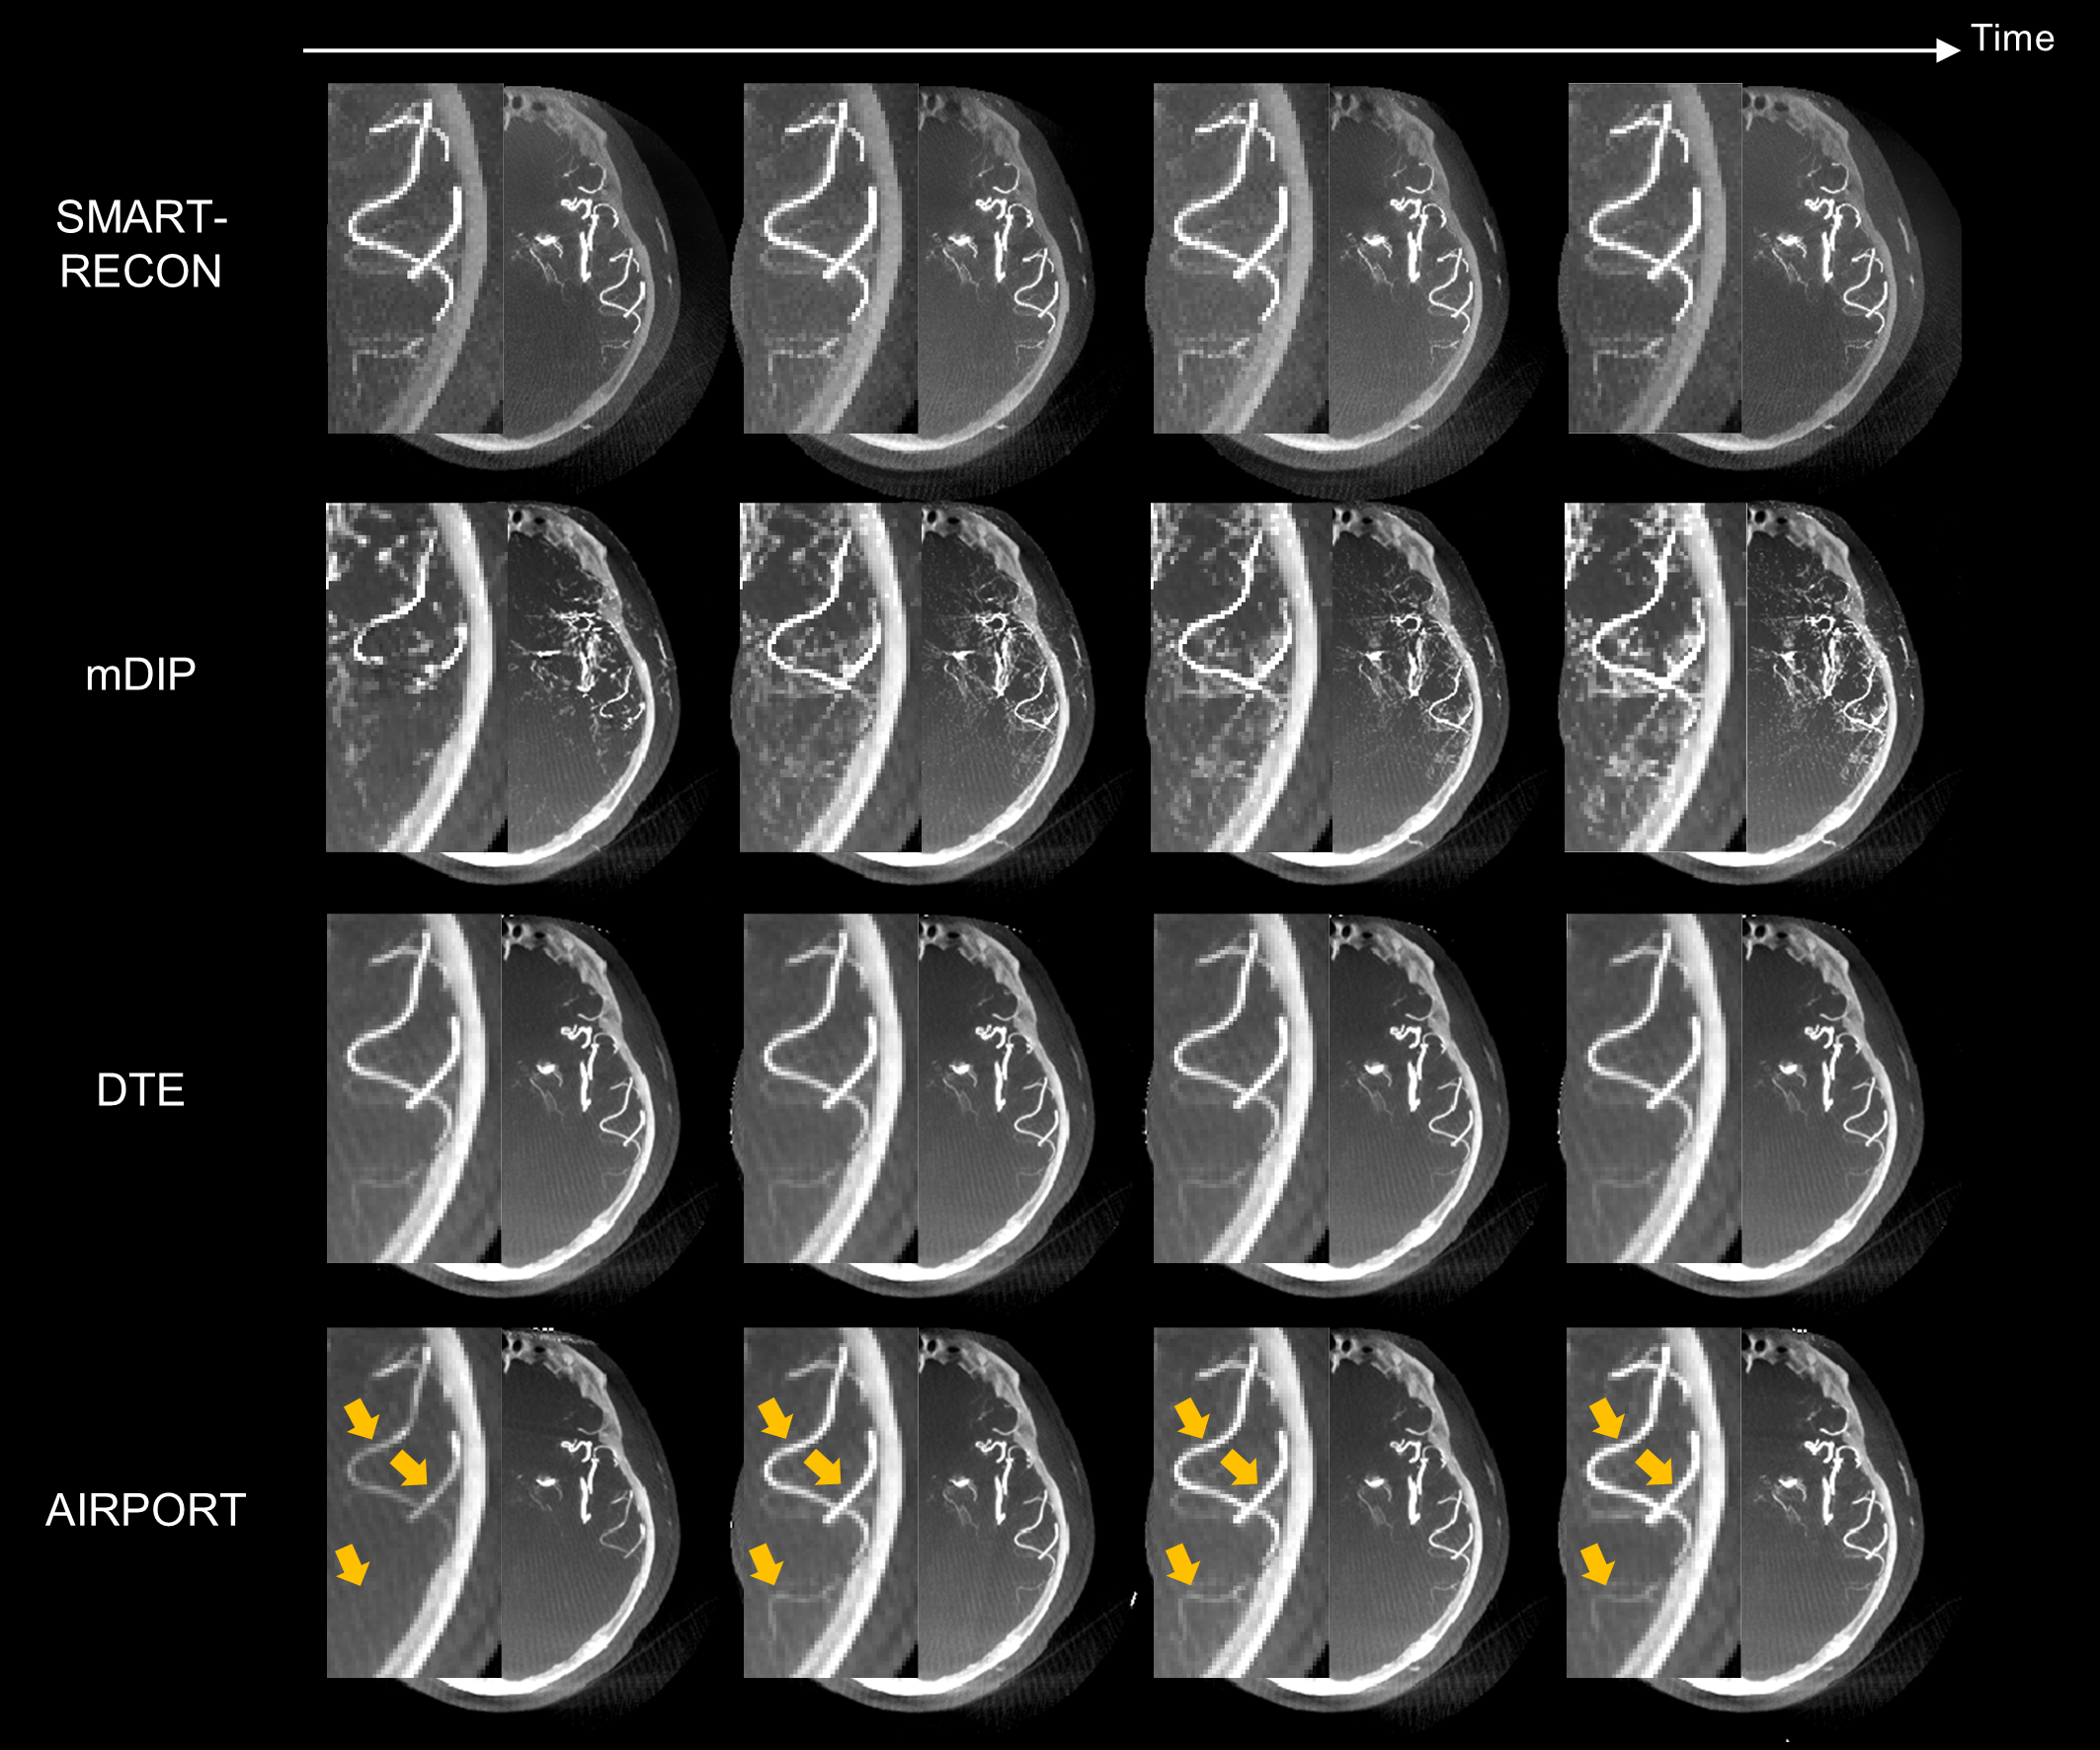

为实现上述想法,本文提出数据一致性约束的深度时间维度外插方法,利用数据一致性约束学习最优外插规则以提高时间分辨(如图2所示)。提出方法的创新性在于:(1)该方法CT时间分辨提高至系统极限(即获取单个视角投影数据所需的时间---诊断CT0.1毫秒或C臂锥束CT25毫秒),从而同时最小化时间平均误差和数据不完备误差;(2)该方法适用于单个短扫描数据采集协议和非稀疏的成像任务;(3)该方法显式地使用每个患者测量投影数据,使得学到的外插规则对每个患者来说是最优的(如图3所示)。

3. 人体实验数据结果如黄色箭头所示,提出的AIRPORT方法能够正确地重建由造影剂注射导致的动脉强度值的变化。